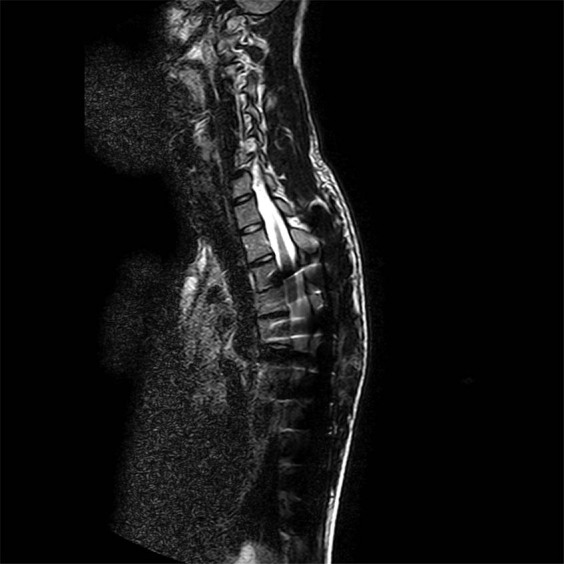

At the ER, a conventional X-ray of the spine was performed, which showed an intact position of the spinal rods. The following day a magnetic resonance imaging (MRI) of the whole spine was performed, but due to artifacts caused by the metallic components used for the scoliosis, the images could not be accurately evaluated. The cervical and lumbar/sacral part of the spine which could be evaluated well (C1-T2 and L2-S5) showed no abnormalities. From T2 to L2, the myelum was hardly visible and no definite conclusions could be drawn from these images (Figs. 1 and 2).

Fig. 1.

T2 weighted sagittal MRI images of the cervical and thoracic spine; due to artifacts the myelum cannot be evaluated properly.

Fig. 2.

T2 weighted sagittal MRI images of the thoracic, lumbar, and sacral part of the spine; due to artifacts the myelum cannot be evaluated properly.